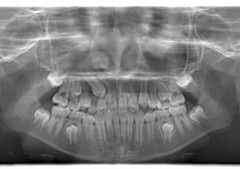

小児期ケース:反対咬合+上顎両側3番埋伏歯

(受け口+右上3番目の永久歯が埋まってしまい、はえてこない)

治療法:上顎急速拡大装置+クリアスナップ+フェイスマスク+上顎右側3番は開窓萌出誘導